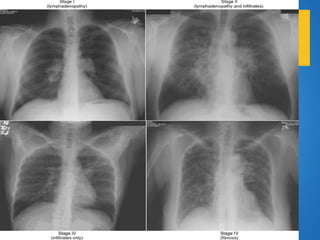

+ STAGE I

Thoracic Lymphadnopaty. Normal lung

+ STAGE II

Hilar and mediastinal Lymphadnopaty. Abnormal

lung parenchyma. ( 30% )

+ STAGE III

Abnormal lung parenchyma. No

Lymphadenopathy. ( 15% )

+ STAGE IV

Extensive pulmonary fibrosis is typically worst in

the upper lobes.

Broad bands of fibrosis in the upper lobes